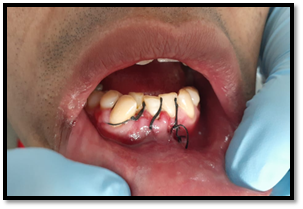

Sutura

Vicril 0000, se suturó primero las papilas interdentales, luego la liberatríz. Siendo un numero de 4 puntos simple de sutura.

Imagen 12. Sutura.

Imagen 13. Control posoperatorio.

Fue trasladado al área de

recuperación, para vigilar los signos vitales del paciente.